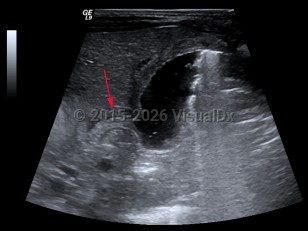

Hypertrophic pyloric stenosis

Hypertrophic pyloric stenosis (PS) is a narrowing of the pyloric lumen due to tissue hypertrophy and scarring. The resultant intestinal narrowing leads to gastric outlet obstruction and bowel obstruction. Although hypertrophic PS can very rarely occur in children and adults, this summary is focused on infantile hypertrophic PS. Patients present with emesis, usually within the first several months of life.

PS is predominantly seen in males (approximately 4:1) and presents typically at 2-7 weeks of life with nonbilious, postprandial projectile emesis and dehydration. Children of parents who had PS have a 20% increased risk of developing PS, suggesting a genetic component, although no clear genetic etiology has been identified.

The complications of PS are due to dehydration and malnutrition. Patients often present with lethargy, failure to thrive, and a hypochloremic, hypokalemic metabolic alkalosis.